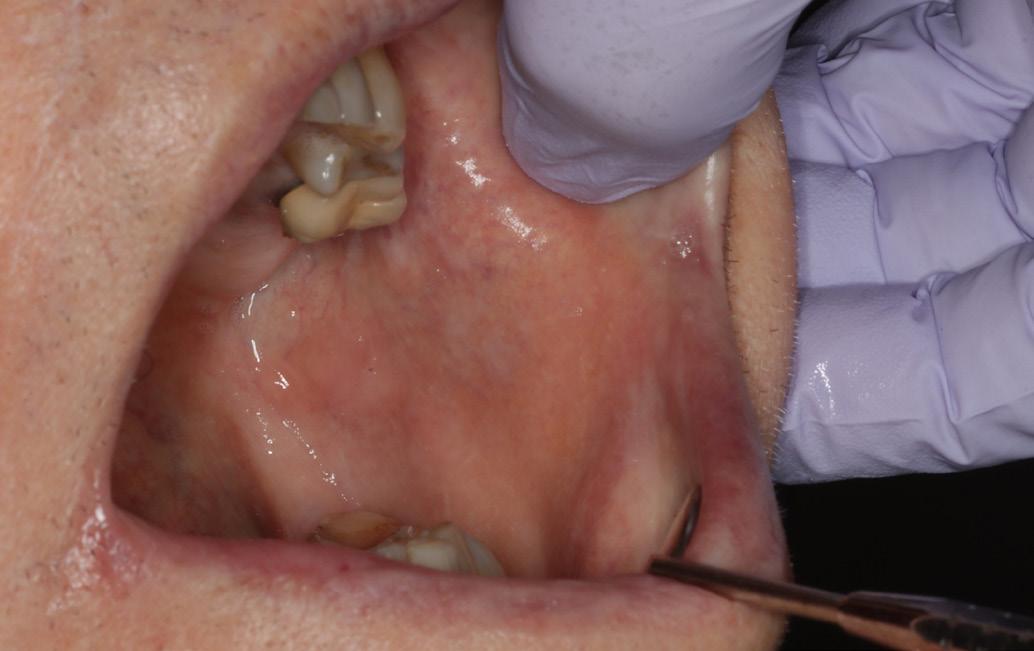

Oral examination revealed several shallow ulcers with erythematous borders affecting the buccal mucosa and the lateral borders of the tongue (Fig. 1). The patient reported significant discomfort while eating and speaking. Blood investigations were unremarkable. He was prescribed dexamethasone mouthwash and Difflam rinse, but there was no improvement. Methotrexate-induced oral ulceration was suspected. The patient’s rheumatologist was contacted, and methotrexate was temporarily withheld. Supportive therapy

Multiple painful ulcers on the buccal mucosa and lateral border of the tongue in a patient taking low-dose methotrexate.

Multiple painful ulcers on the tongue and buccal mucosa in an 80-year-old female taking methotrexate and folic acid, resistant to initial topical therapy and antifungal treatment.